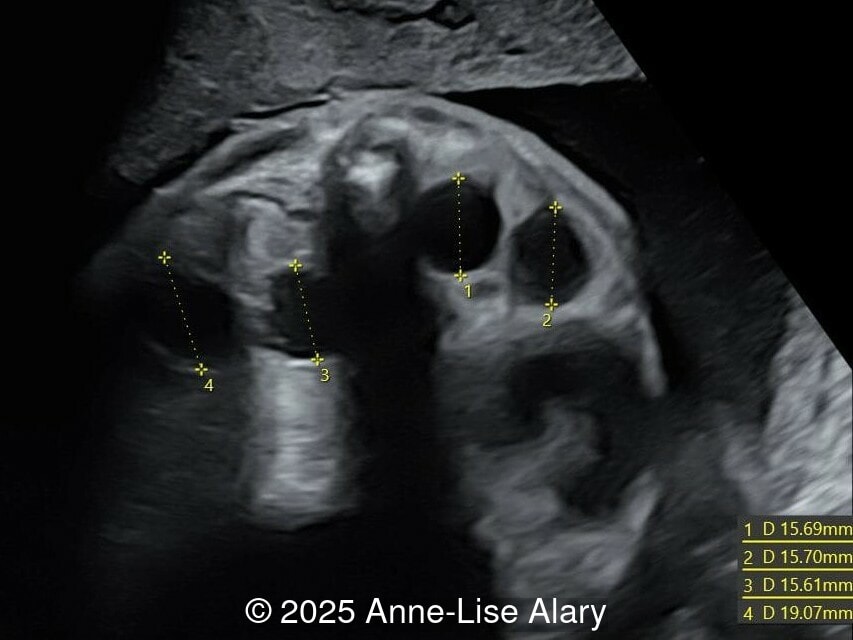

Axial image of the perineum

Image 4 Axial image of the perineum

Our prenatal ultrasound revealed a male fetus with megabladder, dilation of both ureter and kidneys, and thinned kidney parenchyma consistent with Lower Urinary Tract Obstruction (LUTO).  Additional findings suspected on ultrasound and confirmed on computed tomography included:

The diagnosis of PBS is often made in the second trimester of pregnancy, although it has been described as early as 11 weeks of gestation [20]. The most frequent ultrasound findings are a large, thin-walled bladder accompanied by bilateral hydroureter/hydronephrosis, dysplastic kidneys with echogenic renal parenchyma and renal cortical cysts, and abdominal wall laxity which is better viewed after bladder decompression [21]. Cryptorchidism can be detected prenatally by 28 to 30 weeks gestation when the testes descend into scrotum. There may be a patent urachus, visible as a cystic connection between bladder and umbilicus. Oligohydramnios is a frequent finding, which makes it difficult to visualize the associated anomalies.